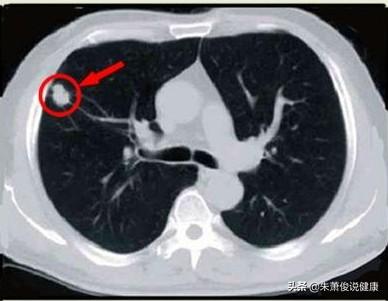

Knötchen werden in feste und gemahlene Glasknötchen unterteilt

Lungenknoten werden je nach ihrer Dichte in verschiedene Typen eingeteilt: Knoten mit höherer Dichte, die auf dem CT der Brust als weiße Punkte erscheinen, werden als solide Knoten bezeichnet, während Schliffknoten eine geringere Dichte haben und wie Wasserdampf auf dem Glas aussehen. Glasschliffknötchen, insbesondere reine Glasschliffknötchen, sind in der Regel bösartiger.